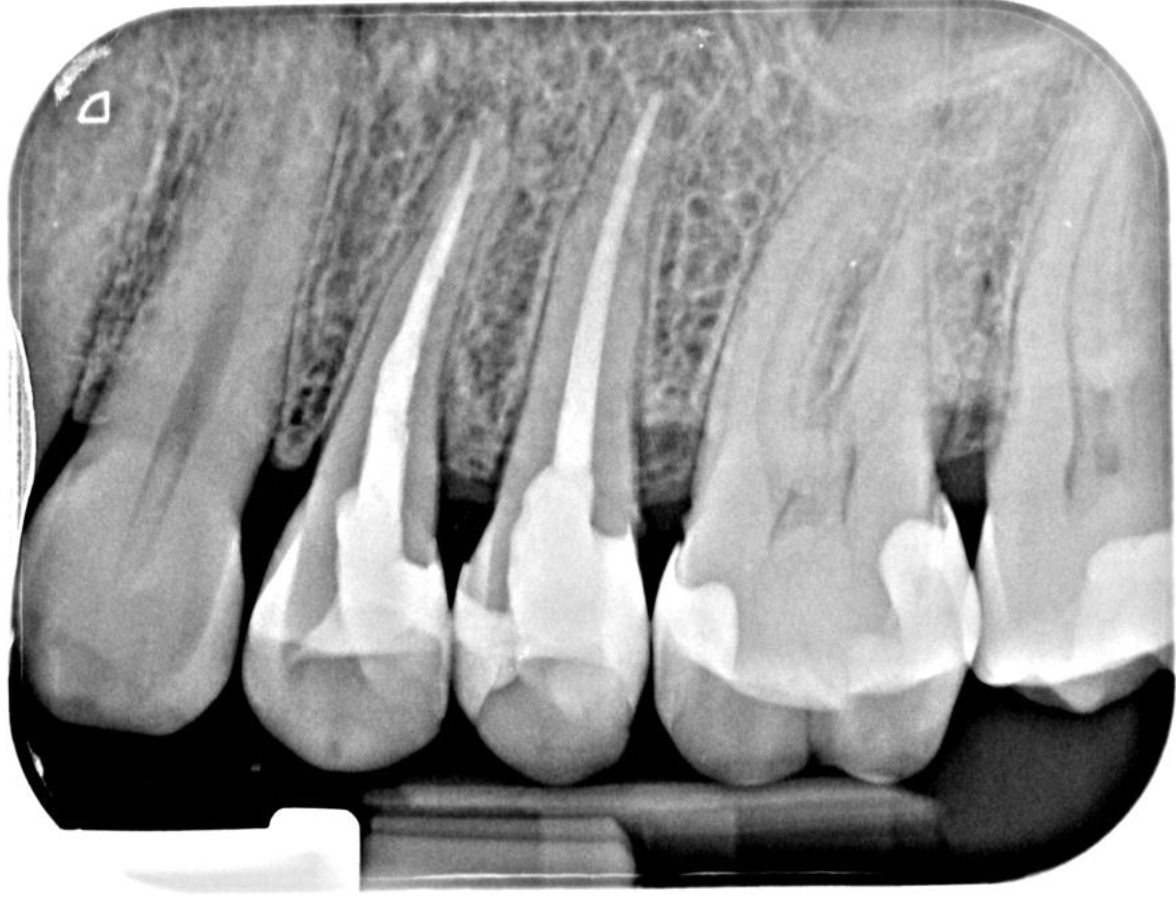

Pre-op IOPA & CBCT

This delightful lady was referred to me as she had recurrent pain and a firm apical swelling around her previously root-treated UL4. Upon viewing the IOPA, at first glance, this case appeared to have been adequately filled. However, CBCT review (shown above) highlighted a deep apical split of the main canal and an unfilled buccal branch, which seems like the most obvious reason for failure in this case.

Having this information preoperatively made the management of this case far more predictable and underlines why a small field of view high-resolution CBCT scan can be invaluable in the management of most re-treatment cases and arguably most primary cases too. Please follow the link for the most current guidance on the use of CBCT in endodontics (https://onlinelibrary.wiley.com/doi/10.1111/iej.13187). At the first visit, the existing root filling was removed using Reciproc blue R25 and prepped using R40 rotary files and the previously unfilled buccal branch was prepared with the reduced taper (4%) VDW Rotate 1504, 2005 and 2504 files, which is one of my favourite file systems. After lots of irrigation and PUI, the tooth was dressed using calcium hydroxide, and the tooth was well sealed for a month. The aim of this was to try and reduce the swelling and alleviate this lady’s symptoms, which it did really nicely. At the second visit, the tooth was further disinfected and re-obturated using WVC and TotalFill BC sealer Hiflow. It was then returned to the RD for cuspal coverage without delay. I plan to review this case in a year's time, so I will update this case study with new radiographs when I have them.